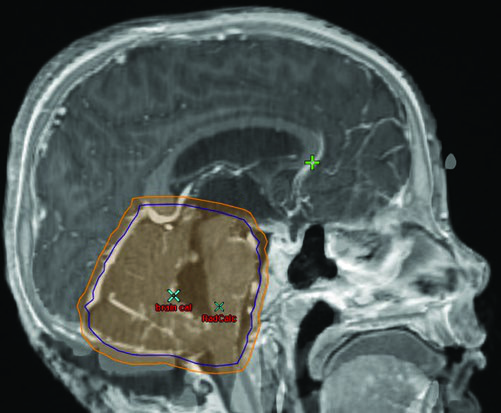

Germinoma puro: irradiación ventricular y boost

La planificación exige RM pre y posoperatoria de 1–3 mm de espesor de corte cubriendo cerebro y columna. Los marcadores séricos y en LCR de beta-hCG y alfa-fetoproteína son fundamentales para descartar componente no germinomatoso: cualquier elevación de AFP reclasifica el tumor como NGGCT. En el protocolo ACNS 1123, los pacientes con beta-hCG sérica o en LCR superior a 100 mIU/mL fueron tratados como NGGCT.

Los germinomas bifocales — compromiso simultáneo supraselar y pineal — se tratan como enfermedad localizada con irradiación ventricular total seguida de boost de campo involucrado. El volumen blanco incluye el tumor prequimioterapia, cualquier enfermedad residual y todo el sistema ventricular. Delinear la enfermedad prequimioterapia en el momento de la planificación inicial es crítico, porque el volumen de boost frecuentemente se extiende más allá de los límites ventriculares normales.

El boost CTV se define como GTV prequimioterapia + 1 a 1,5 cm. La inclusión de la cisterna prepontina es opcional, pero debe considerarse en pacientes sometidos a ventriculostomía o con tumores supraselares voluminosos.

Esquemas de dosis para germinoma puro

Cuando la radioterapia es la modalidad única, el volumen ventricular recibe 21 a 24 Gy con boost hasta 45 Gy en el sitio tumoral prequimioterapia. Una fracción de 1,5 Gy es preferida por muchos centros dado el buen pronóstico y el deseo de minimizar la toxicidad neurocognitiva a largo plazo, aunque 1,8 Gy por fracción es igualmente razonable.

Con quimioterapia neoadyuvante y respuesta completa del primario, la dosis ventricular desciende a 21 Gy con boost de 9 a 15 Gy, totalizando 30 a 36 Gy en el tumor primario. El estudio ACNS 1123 investigó la reducción de la dosis ventricular a 18 Gy: no hubo fracasos ventriculares en los 74 pacientes evaluables, pero el estudio no logró demostrar no-inferioridad frente al umbral de 95% de supervivencia libre de progresión a 3 años. Los pacientes con respuesta parcial o enfermedad progresiva necesitan boost hasta 36 a 45 Gy en el tumor primario.